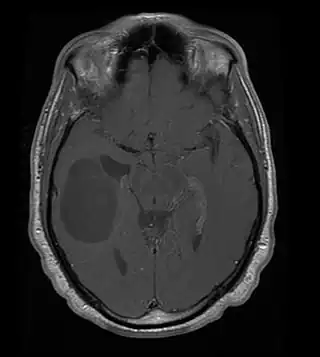

![]() Oligodendroglioma (zona hipodensa u oscurecida de la izquierda), resonancia magnética. | ||